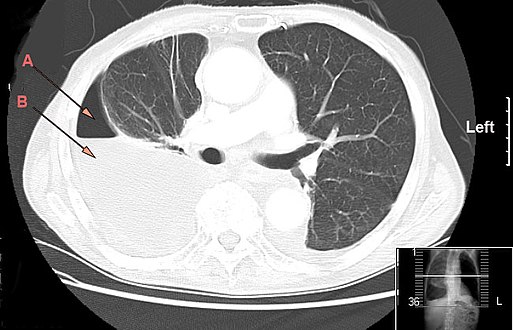

An empyema (/ˌɛmpˈmə/) is a collection of pus within a naturally existing anatomical cavity. For example, pleural empyema is empyema of the pleural cavity. It must be differentiated from an abscess, which is a collection of pus in a newly formed cavity. The term is from Greek ἐμπύημα, "abscess".

Lungs[edit | edit source]